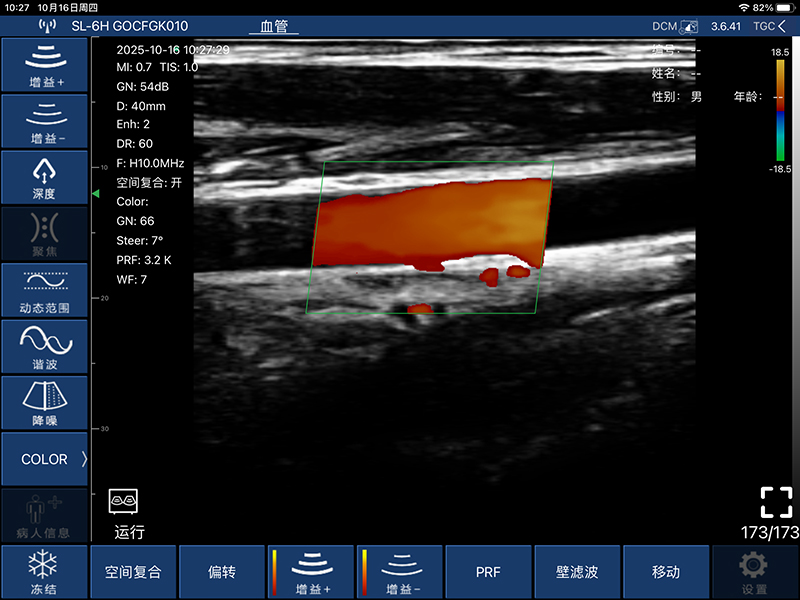

• 扫描方式:电子阵列扫描

• 探头频率:7.5/10MHz

• 扫描深度:20-100mm,可调

• 显示模式:B、B/M、Color、PW、PDI